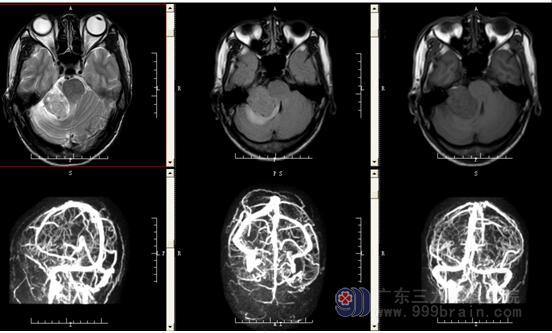

入院完善相关检查;2.影像学检查提示:颅脑CTA示:右侧桥小脑角区占位性病变内存在少许小血管,考虑为听神经鞘瘤可能,请结合MRI检查颅脑MR示:1.右侧桥小脑角区占位病变,考虑为听神经鞘瘤;2.左侧乙状窦及横窦显示变细,考虑发育变异,余脑MRV检查未见异常。3.于2018.06.20日行右侧桥小脑角占位性病变切除术+ICP探头置入术。

术前CT及脑MRV结果示1.右侧桥小脑角区占位病变,考虑为听神经鞘瘤;2.左侧乙状窦及横窦显示变细,考虑发育变异。

术前MR报告示右侧桥小脑角区示一团块状长T1稍长T2信号影,FLAIR序列呈等信号,大小约47mm×32mm×35mm;增强后呈明显强化,邻近右侧听神经增粗、强化;邻近右侧小脑半球示斑片状长T1长T2信号影,FLAIR序列呈高信号。